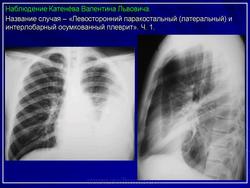

Левосторонний паракостальный осумкованный плеврит.

2. Осумкованный паракостальный плеврит.

Пристеночные (паракостальные) осумкованные плевриты являются результатом неполного рассасывания свободного экссудативного паракостального плеврита или транссудата, свои широким основанием прилежат к поверхности ребер.

В типичных случаях рентгенологическая картина пристеночных осумкований довольно характерна.

Они, скиалогически проявляясь синдромом «ограниченного затемнения», имеют форму теней, примыкающих широким плоским основанием к реберному краю.

Верхушечный (апикальный) осумкованный плеврит - редкая локализация осумкованных плевритов (иллюстрация 5). Он наблюдается чаще всего у больных туберкулезом, сопровождающимся поражением верхушки лёгкого и сморщиванием легочной ткани. Также осумкованный плеврит данной локализации довольно часто имеет место при доброкачественных и злокачественных опухолях верхнего отдела средостения, верхних ребер, плевры. Довольно редко апикальные плевриты могут иметь место при травмах.